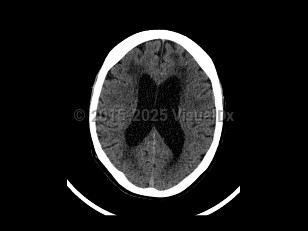

Normal pressure hydrocephalus (NPH) is a common neurologic disorder resulting in slowly progressive gait abnormalities, cognitive deterioration, and urinary incontinence.

The syndrome is often divided into 2 groups, idiopathic and secondary, based on etiology. Idiopathic NPH is thought to occur due to increased resistance to cerebrospinal fluid (CSF) absorption, leading to temporary elevations in intracranial pressure and mechanical compression of structures adjacent to the ventricles. However, the underlying etiology of idiopathic NPH has not yet been identified. Secondary causes of NPH include the sequelae of brain infections such as meningitis, trauma, or subarachnoid hemorrhage. This article will focus on the diagnosis, evaluation, and treatment of idiopathic NPH.

The incidence of NPH increases with advancing age, and most patients are over the age of 60. There is no difference in incidence between men and women. NPH has an estimated incidence of 1-5 cases per 100 000 people per year. Its prevalence is reported to be less than 1% in persons under the age of 65, and up to 3% for persons aged 65 or older. Among individuals with dementia, the incidence of NPH is thought to be between 2% and 6%.